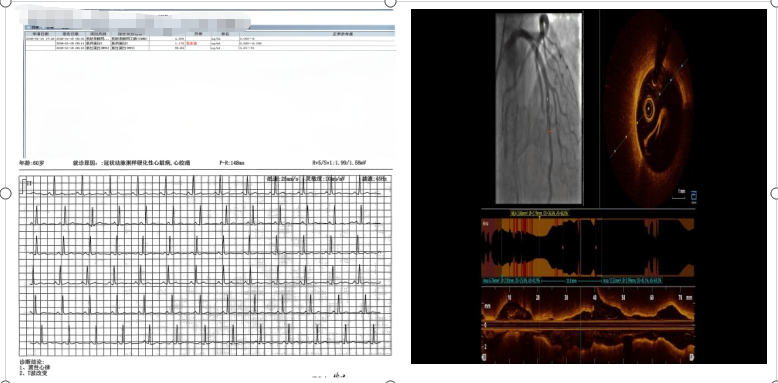

为破解诊断迷雾、明确病因,医疗团队再次为患者实施冠脉造影,并创新性联合高分辨率光学相干断层成像(简称OCT技术,一种精准观察血管内部病变的先进检查方式)进行精准检查,最终成功锁定病因——患者冠状动脉前降支远段存在肌桥合并斑块破裂,据此确诊为非阻塞性冠状动脉心肌梗死(MINOCA,“隐形心梗”)。据悉,MINOCA是一种特殊类型的心肌梗死,约占所有心梗病例的5%-10%,尤其在中青年、女性及无典型危险因素人群中易发生漏诊。其核心特征是,患者虽有明确的心肌梗死表现,但冠脉造影未发现明显阻塞性病变,因此常被误判为“假心梗”或其他疾病。

转至新桥医院后,科室赵晓辉主任第一时间带领医疗团队为患者开展全面评估。检查结果显示,患者心肌损伤标志物显著升高,心电图也明确提示心肌梗死,但紧急冠脉造影检查却发现,其主要血管并无超过50%的严重狭窄——这一结果与此前当地医院的检查结论、患者典型的心肌梗死症状形成鲜明矛盾,诊疗工作一度陷入僵局。不过,患者夜间仍频发静息胸痛,需舌下含服硝酸甘油才能缓解,这一关键症状让医疗团队坚定了深入探究、破解病因的决心。